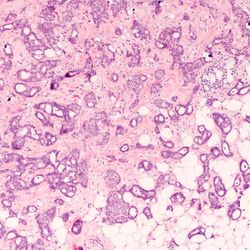

Leveraging Next-Gen IHC Tools to Advance Precision Oncology Research

Harnessing the power of multiplexing and RNA–protein studies could help design targeted cancer treatments